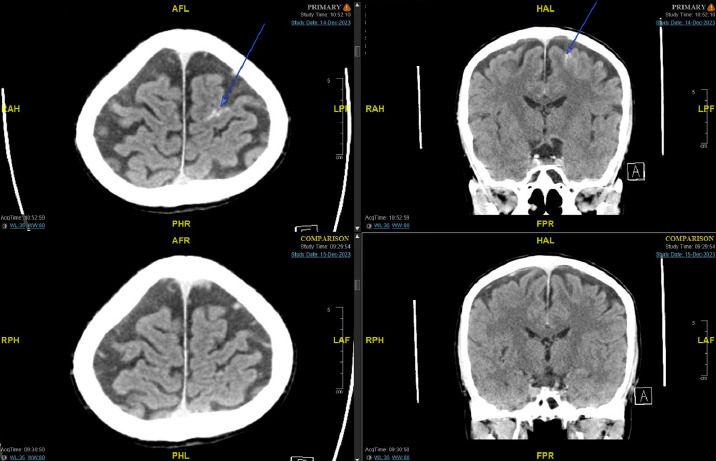

迟发性慢性硬膜下血肿(cSDH)是外伤性脑损伤(TBI)后常见但潜在严重的并发症。轻度脑外伤通常由初级保健提供者(pcp)管理,特别是在像马来西亚这样资源有限的大国家,三级神经外科服务可能会延迟。早期识别危险体征和症状并及时转诊对于防止临床恶化至关重要。我们描述的情况下,66岁的男子谁持续轻度头部损伤后,血管迷走神经性晕厥。他最初的脑部CT显示左侧中央前沟有一个小的外伤性蛛网膜下腔出血,24小时后的间隔扫描解决了这个问题。他没有随访就出院回家了。11周后,他出现双侧下肢无力和步态不稳,这促使他的全科医生紧急转诊。重复CT显示双侧急慢性硬脑膜下血肿,肿块效应需要紧急钻孔引流。患者术后表现良好,第4天出院,后续随访无临床或影像学复发。该病例强调了轻度TBI患者延迟cSDH的风险,即使在那些出院时CT扫描正常的患者中也是如此。pcp在识别高危患者、确保有组织的随访和促进及时的专科转诊方面发挥着关键作用。我们提倡更新马来西亚的头部损伤指南,以国际标准为模型,纳入高危患者的常规随访方案。

Delayed chronic subdural haematoma (cSDH) is a common but potentially serious complication following traumatic brain injury (TBI). Mild TBIs are commonly managed by primary care providers (PCPs), particularly in large, resource-limited settings such as Malaysia, where access to tertiary neurosurgical services may be delayed. Early identification of red-flag signs and symptoms and timely referrals are crucial to prevent clinical deterioration. We describe the case of a 66-year-old man who sustained mild head injury following a vasovagal syncope. His initial brain CT revealed evidence of a small traumatic subarachnoid haemorrhage over the left precentral sulcus, with resolution on an interval scan 24 hours later. He was discharged home without follow-up. Eleven weeks later, he developed bilateral lower-limb weakness and unsteady gait, which prompted an urgent referral by his general practitioner. Repeat CT revealed bilateral acute-on-chronic subdural haematomas, with mass effect requiring emergency burr-hole drainage. The patient showed excellent post-operative improvement and was discharged home on day 4, with no clinical or radiological recurrence on subsequent follow-up. This case highlights the risk of delayed cSDH in patients following mild TBI, even in those discharged with a normal CT scan. PCPs play a pivotal role in recognising high-risk patients, ensuring structured follow-up and facilitating timely specialist referral. We advocate for updating the Malaysian head injury guidelines to incorporate routine follow-up protocols for at-risk patients, modelled after international standards.